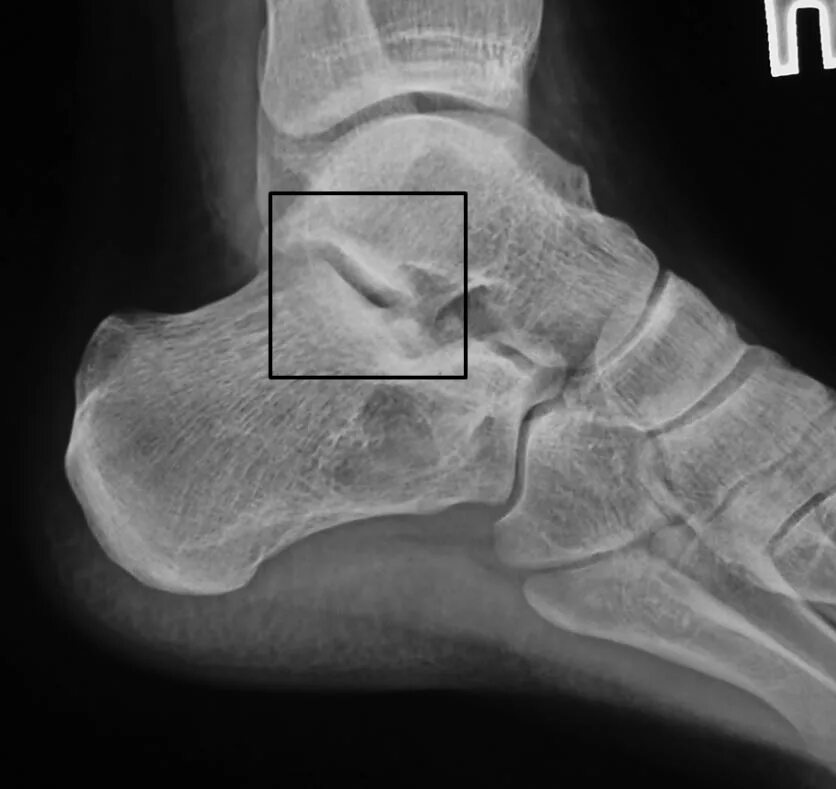

Перелом задней кости стопы